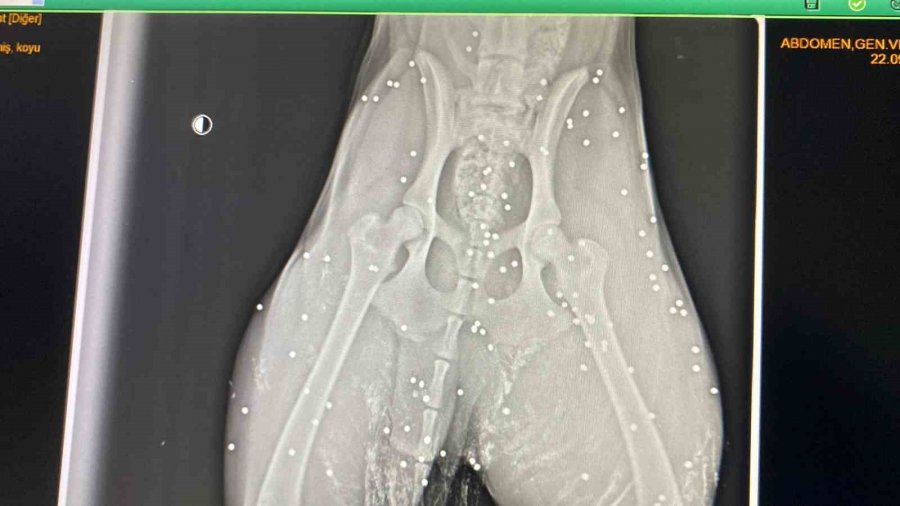

Antalya'nın Aksu ilçesinde silahla vurulan sokak köpeğinin çekilen röntgen görüntüsü adeta şoke etti. Yapılan incelemede köpeğin kalçasında onlarca saçmaya rastlanırken, veterinerde ilk müdahalesi yapılan köpek, bir hayvansever tarafından bakımı üstlenildi.

Polis ekipleri ise şikayet üzerine harekete geçerek olayla ilgili inceleme başlattı. Köpeğin durumu hakkına açıklama yapan Veteriner Mustafa Gülcü, "Köpek bize silahla yaralanma şikayetiyle geldi. Biz hemen ilk müdahalesini yaptık. Ardından röntgen çektik, incelediğimizde çok sayıda saçmaya rastladık. Yakın mesafeden sıkılsa sinirlerine zarar verebilirdi" sözlerine yer verdi.

"Röntgen görüntülerine baktığımızda köpeğin arka kısmı tamamen yok"

Yaşananları anlatan Gülhan Tünay, "Sabah saatleriydi iki el silah sesi duydum. Ardından köpeği acı içerisinde buldum. Eşime seslenerek eyvah köpeği vurdular dedim. Köpek arka tarafı kanlar içinde geldi. Seçim gecesi de bir köpek vurulmuştu, o köpek şuan ampute oldu. Veterinere söyledim gelip aldılar. Daha sonra polisi aradım ve köpeği vuran kişiden şikâyetçi oldum. Röntgen görüntülerine baktığımızda köpeğin arka kısmı tamamen yok. Kaç tane saçma olduğunu bilmek zor. Şuan durumu çok iyi değil, ilk getirdiğimizde hayati tehlikesi vardı. Şuan serum takılı biz de bekliyoruz. İnşallah özürlü kalmaz. Ne hissettiğini bilmiyorum. İnsanların artık silahlanması önlensin istiyorum" dedi.